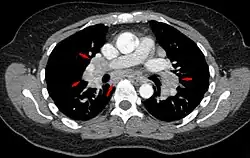

Hilar adenopathy especially on the person's left (AP CXR)

Hilar adenopathy especially on the person's left (coronal CT)

Hilar adenopathy especially on the person's left (transverse CT)